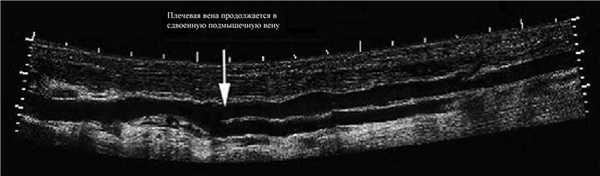

В подмышечной зоне часто можно наблюдать продолженный сегмент удвоенной вены, хорошо видно на УЗИ.

Рисунок. Продольный срез плечевой артерии и вены (1); плечевая артерия и две смежные вены (2).